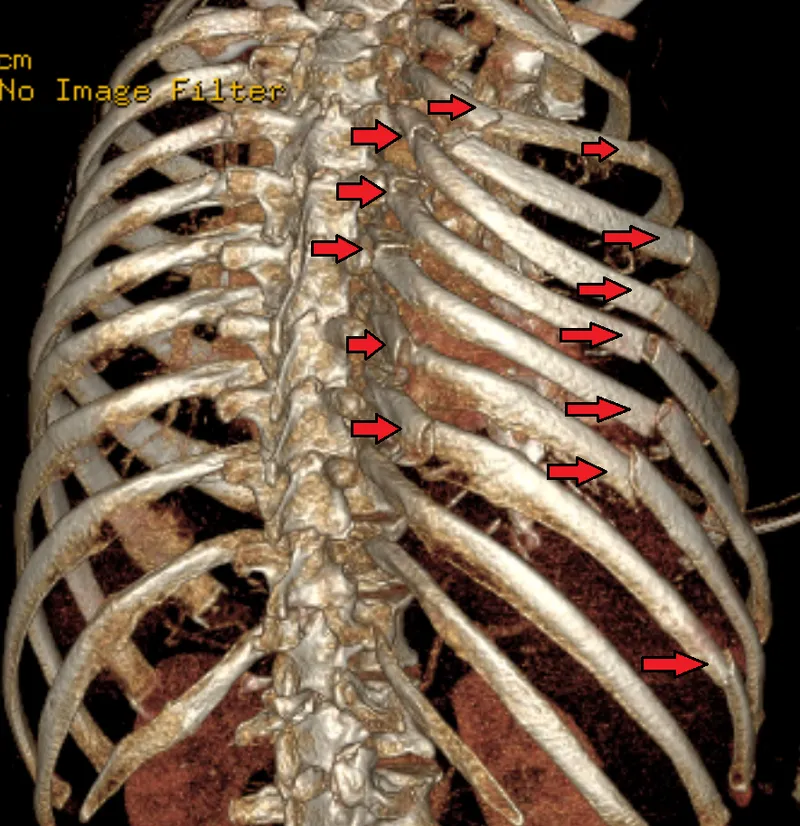

Rib Fractures: Most common chest trauma.

- Complications: Pulmonary contusion, neurovascular/visceral injury.

- Associated injuries by location:

Ribs Associated Injury Potential 1-3 Major vascular (subclavian), brachial plexus, lung 4-8 Lung (pneumothorax, contusion) 9-12 Liver, spleen, kidneys (solid abdominal organs)

⭐ First and second rib fractures are markers of severe trauma and have a high association with vascular and brachial plexus injuries.

Flail Chest:

- Definition: ≥3 consecutive ribs fractured in ≥2 places.

- Key sign: Paradoxical chest wall movement.